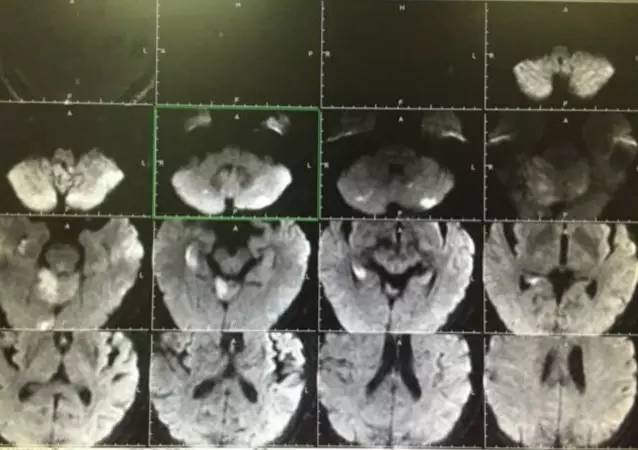

▼术后复查头颅MRI显示小脑蚓部及小脑半球有散在的梗死灶,脑干未见梗死。头颅MRA显示后循环血管通畅。

▼有这样的结果那么病人恢复也一定是很满意的,术后3天患者完全恢复正常无任何神经缺失症状。